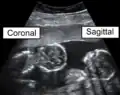

Identical twins at a gestational age of 15 weeks, shown in coronal and sagittal plane, respectively -